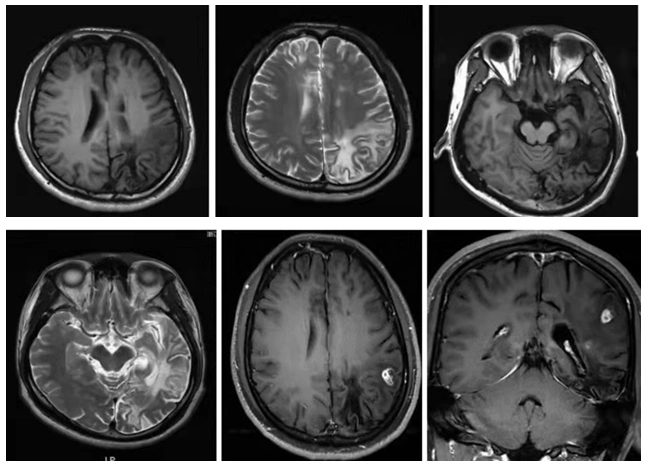

脑囊虫病的头部影像ppt

于人脑内所形成的中枢神经系统寄生虫病,其典 型的头颅磁共振影像为不